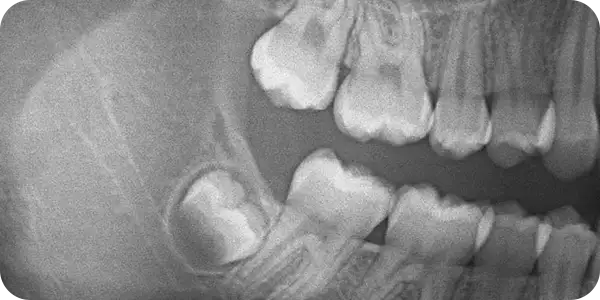

Согласно обобщённым результатам 98 исследований с участием более 183 тыс. человек, ретенция только третьих моляров выявляется у 36,9 % людей [1]. При этом примерно каждый четвёртый стоматологический пациент старше 30 лет имеет сопутствующее соматическое заболевание [2].